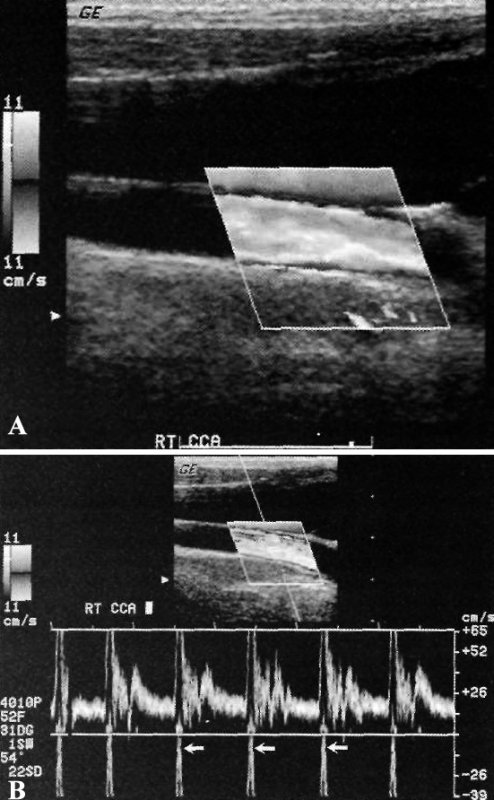

Допплерография сонной артерии: артефакт смешивания

Фото 8. Допплерография сонной артерии: артефакт смешивания. А – допплерограмма общей сонной артерии в норме: поток направлен в сторону датчика, на изображении должен быть красный цвет; так как поток имеет большую скорость и расположен центрально (белый и желтый), он превосходит размер положительной части допплеровской шкалы, поэтому оборачивается с отрицательной стороны. В результате поток визуализируется как направленный от датчика, как в прилежащей яремной вене. В – спектральная допплерограмма общей сонной артерии в норме: небольшая шкала скорости, нормальный пик систолической скорости превосходит размер шкалы и оборачивается вокруг, выходя снизу

Исключить артефакт смешивания можно прежде всего путем повышения PRF (частоты повторений импульса), либо путем снижения частоты допплеровского сдвига (для этого надо использовать датчик низкой частоты).